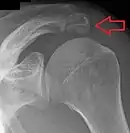

Shoulder

Os acromiale.

• An os acromiale forms when any of its four ossification centers fail to fuse. These four ossification centers are called (from tip to base) pre-acromion, meso-acromion, meta-acromion, and basi-acromion. In most cases, the first three fuse at 15–18 years, whereas the base part fuses to the scapular spine at 12 years. Such failure to fuse occurs in between 1% and 15% of cases.[23][24] It rarely causes pain.